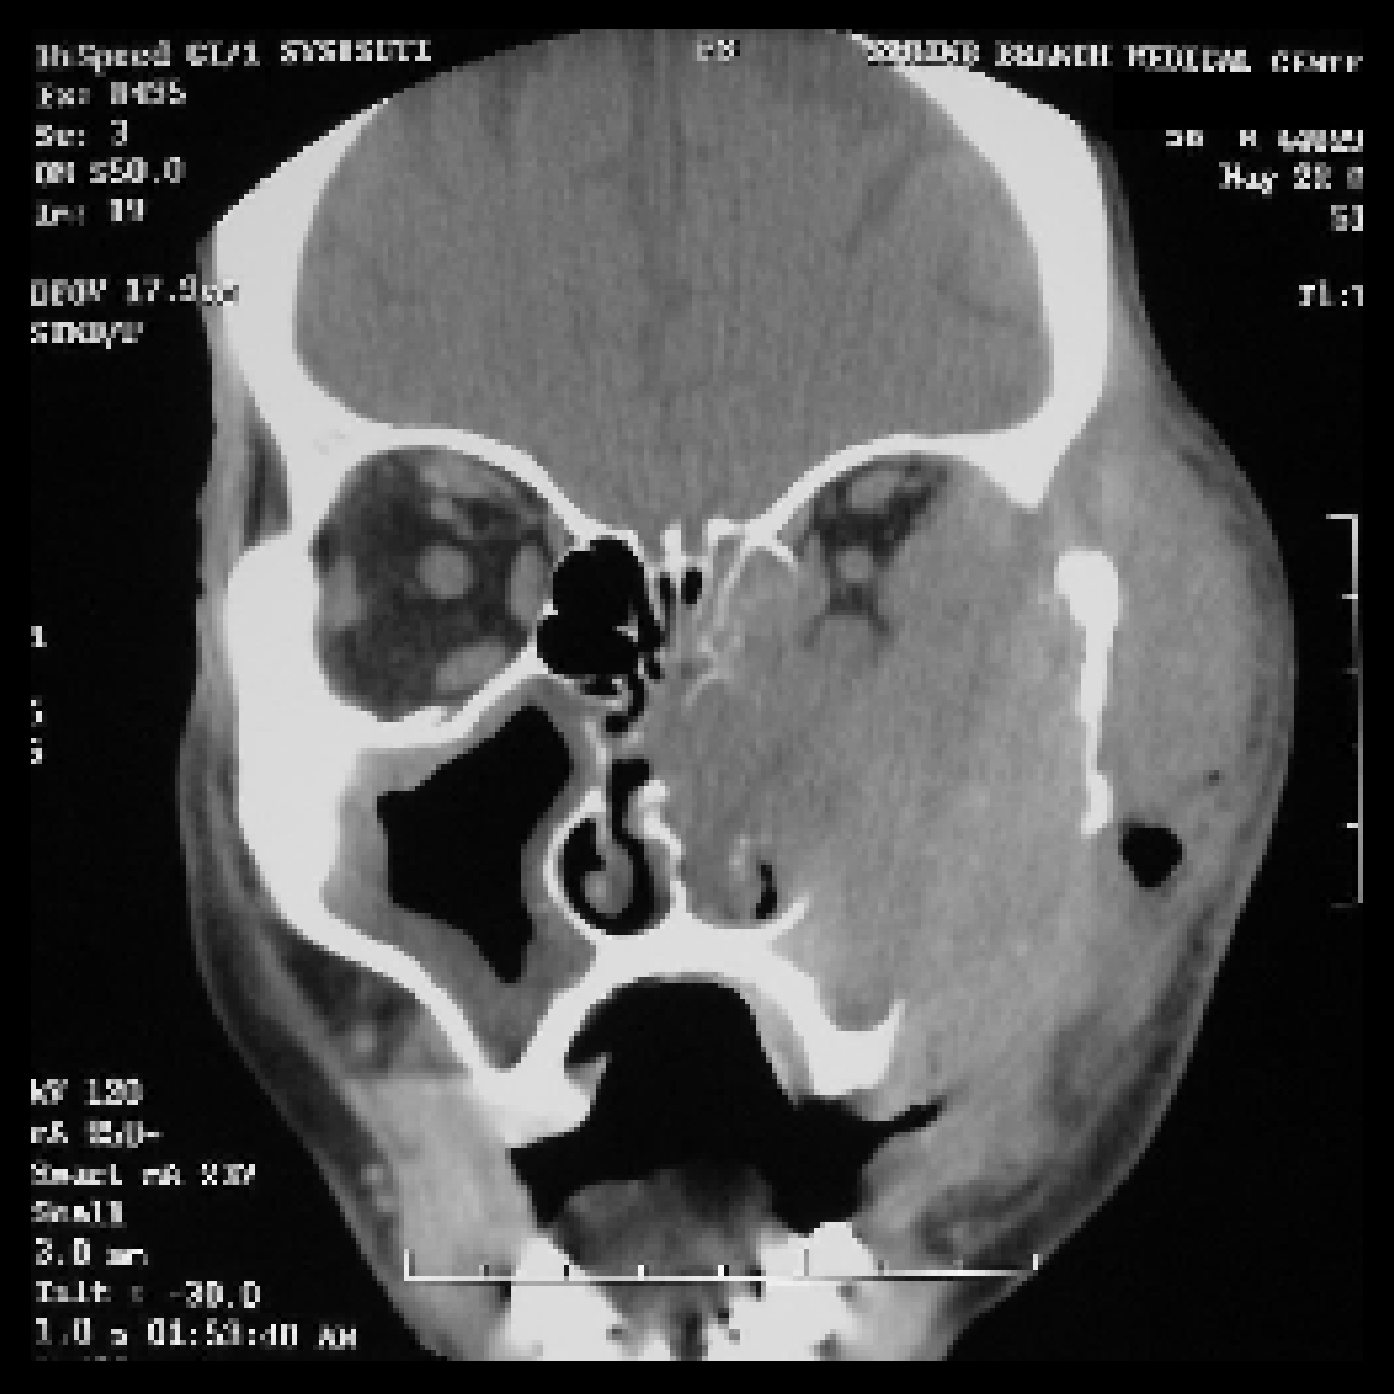

Рак Носа Фото

Рак Носа Фото 80 фотографий